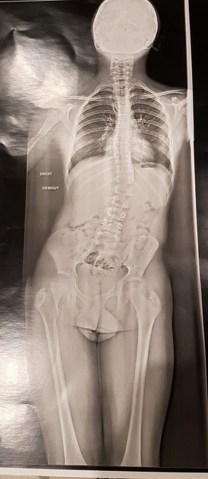

Le jour où ma fille m’a envoyé cette photo de radio j’ai cru à un montage, hélas non c’est bien celle de mon petit fils de 11ans. Elle n’en revenait pas de ne pas avoir vu ça avant ! Pourtant l’été venait de se terminer et il était souvent en slip de bain. Mais personne n’avait remarqué ça et comme je l’ai affirmé au Dr c’est arrivé tout d’un coup ! Il avait beaucoup grandi en quelques mois à peine et ça on l’avait bien vu.

Elle est impressionnante la radio, heureusement que tout semble être rentré dans l’ordre !